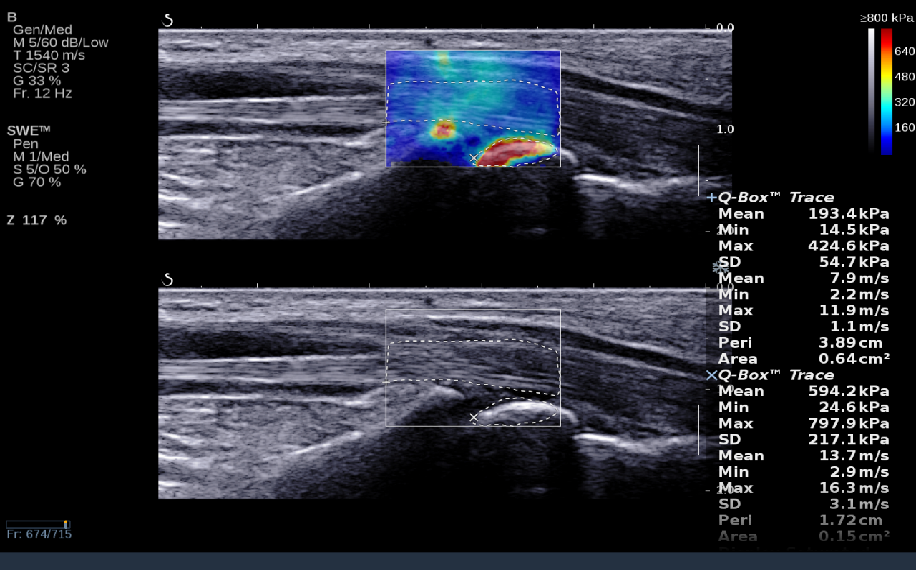

RTSWE实时剪切波弹性成像

?探头发射激励脉冲进行多点动态聚焦,利用马赫圆锥原理,形成大量的剪切波信号?颜色的变化与剪切波的速度相关,可直接体现肌肉肌腱等组织硬度值?实时、全幅、全定量

鉴别诊断、精准分级、定量评价、穿刺引导、疗效评估、随访观察

8a026746049f826559ab090aadef77f.png

9343ee4c6421309eedd3d2c0d2a5f32.png